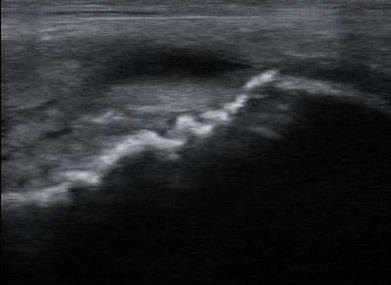

Az ultrahang diagnosztika nagyon nehéz. A felvételen a csontfelszín egyenetlensége látszik (recés, fehér vonal). Krónikus ízületgyulladás során kialakuló csontfelrakódások okozzák. Ezek az elváltozások hamarabb láthatóak ultrahanggal, mint röntgennel.